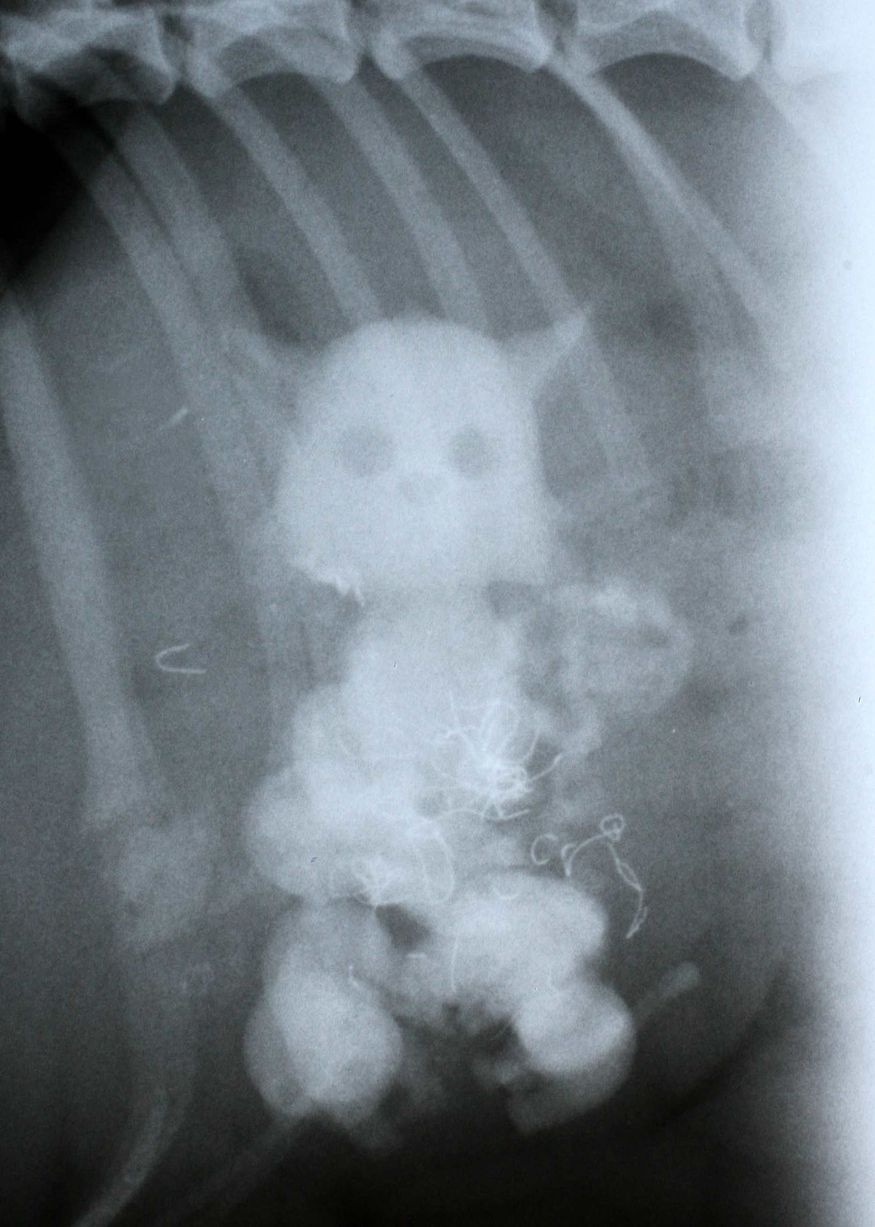

| Các con búp bê trong cơ thể chú chó Alec ở thị trấn Sutton, London, Anh. |